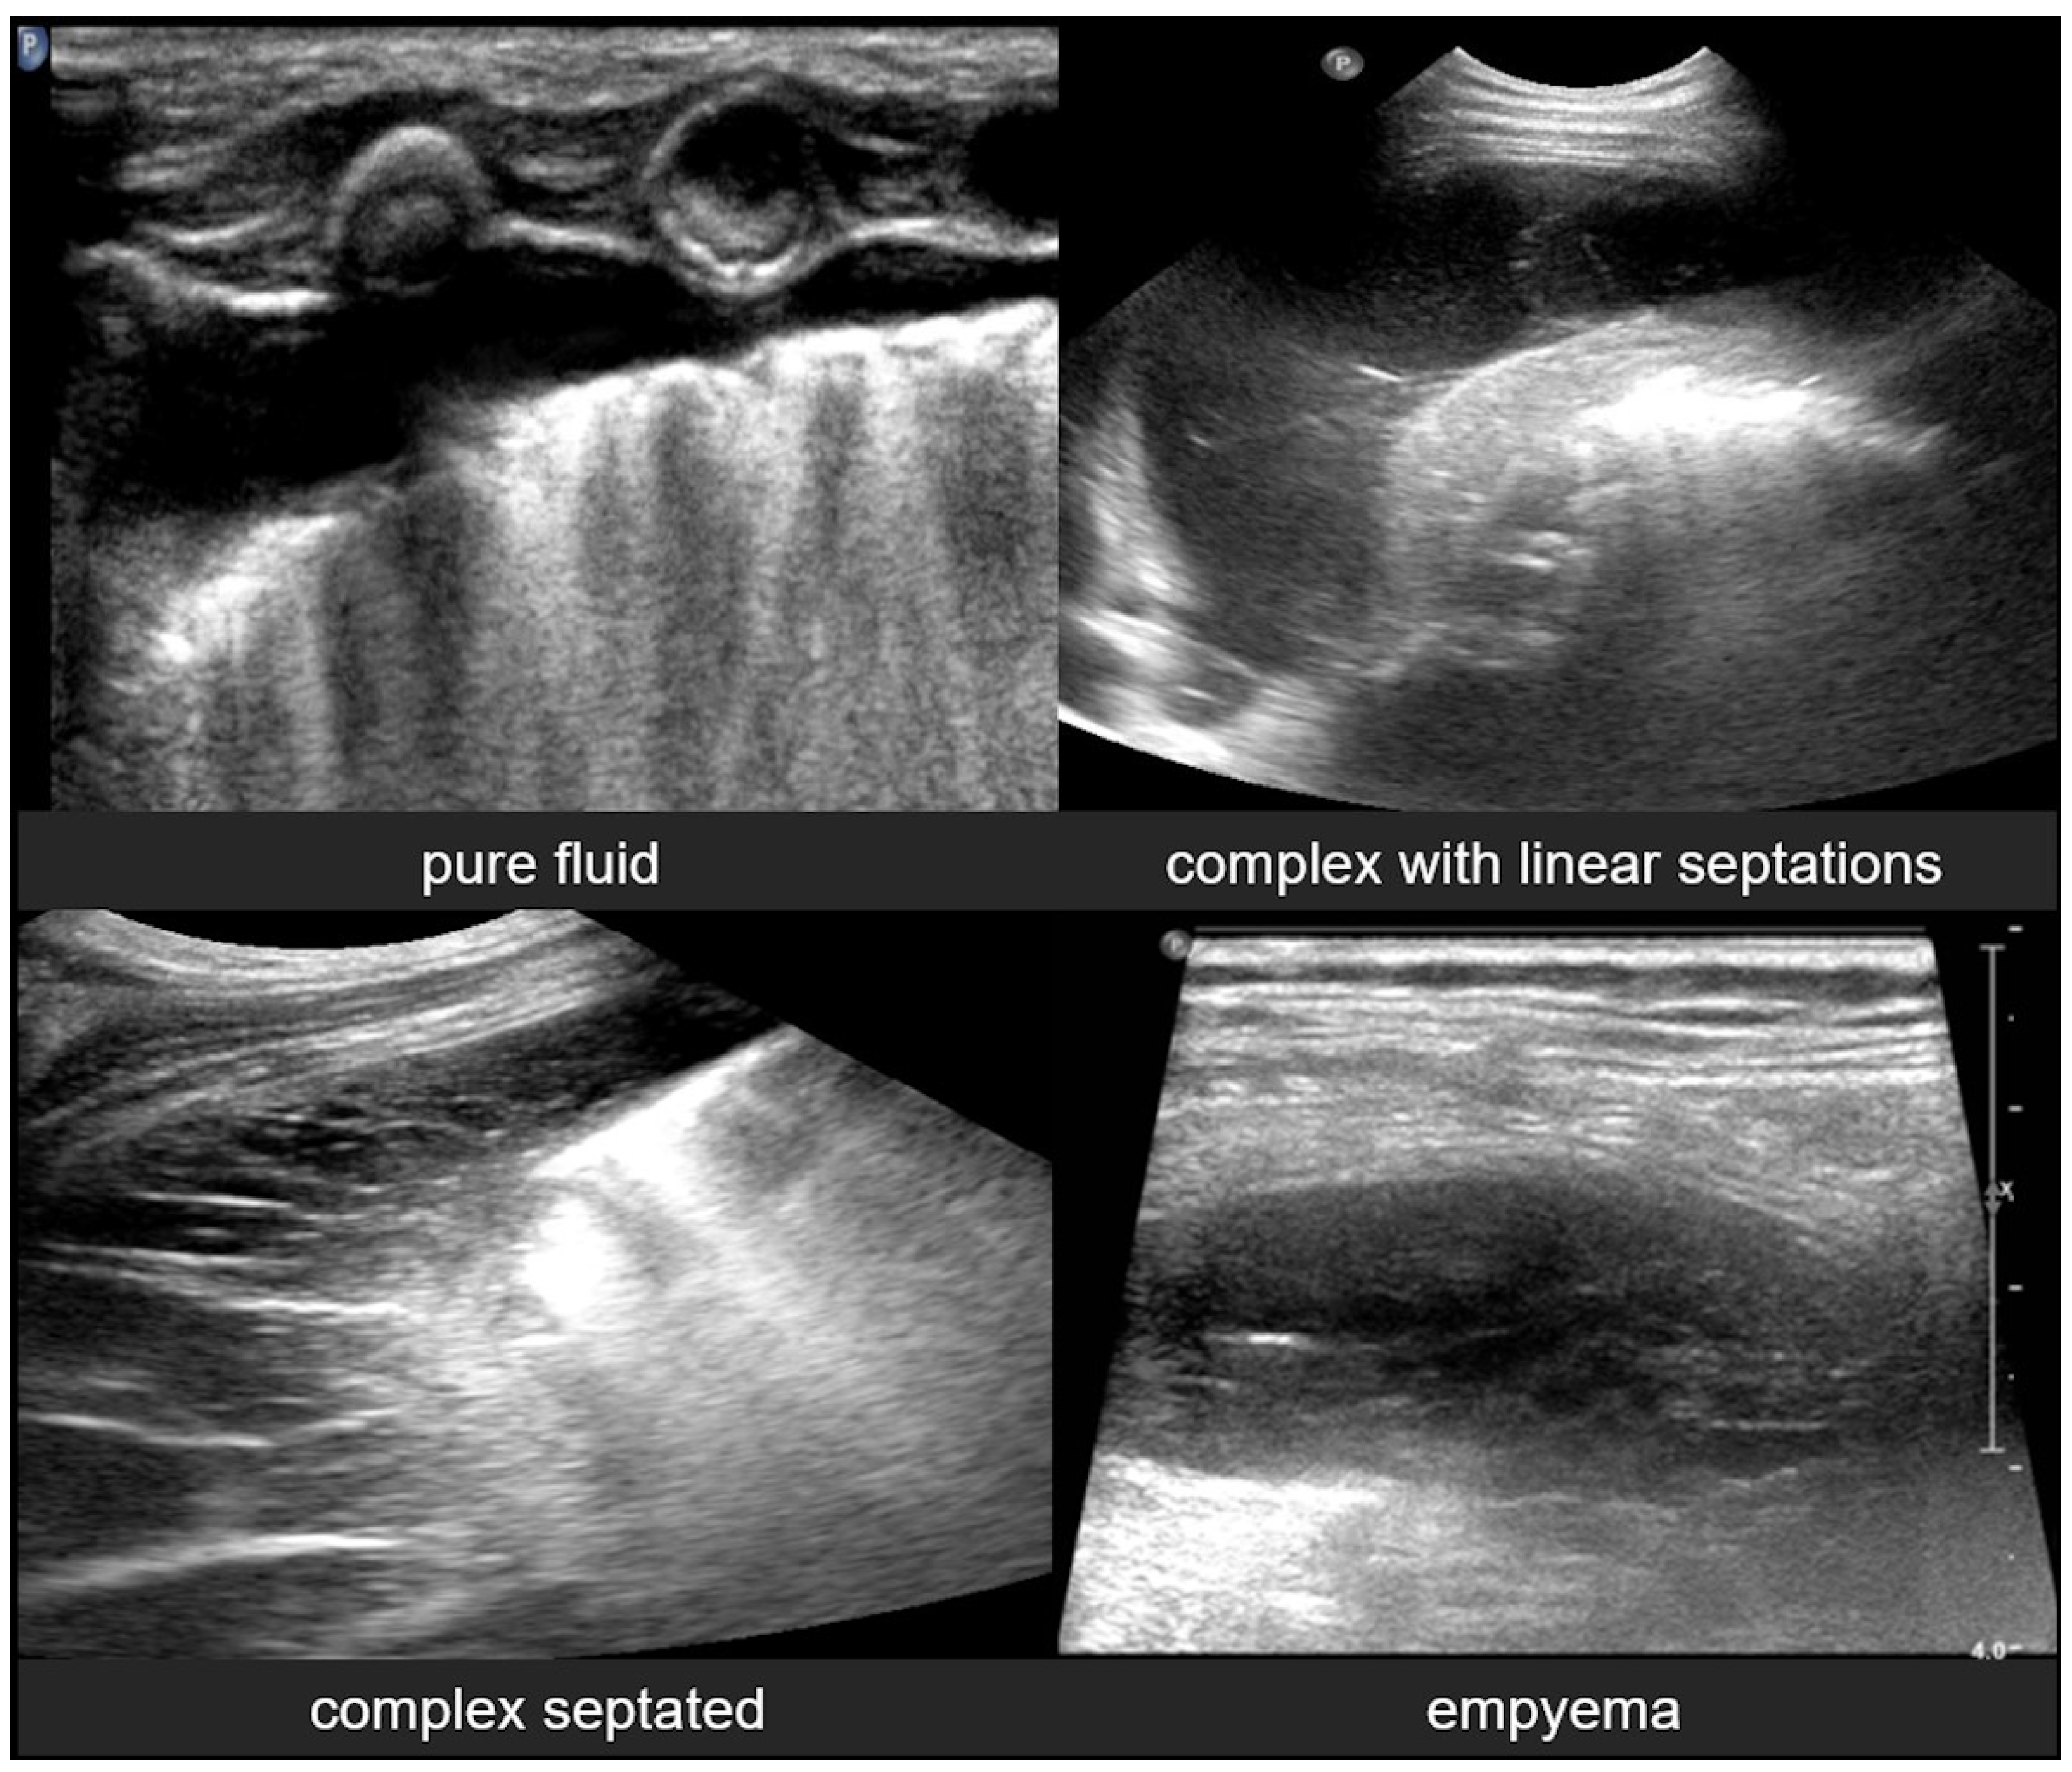

3.2.11. Empyema